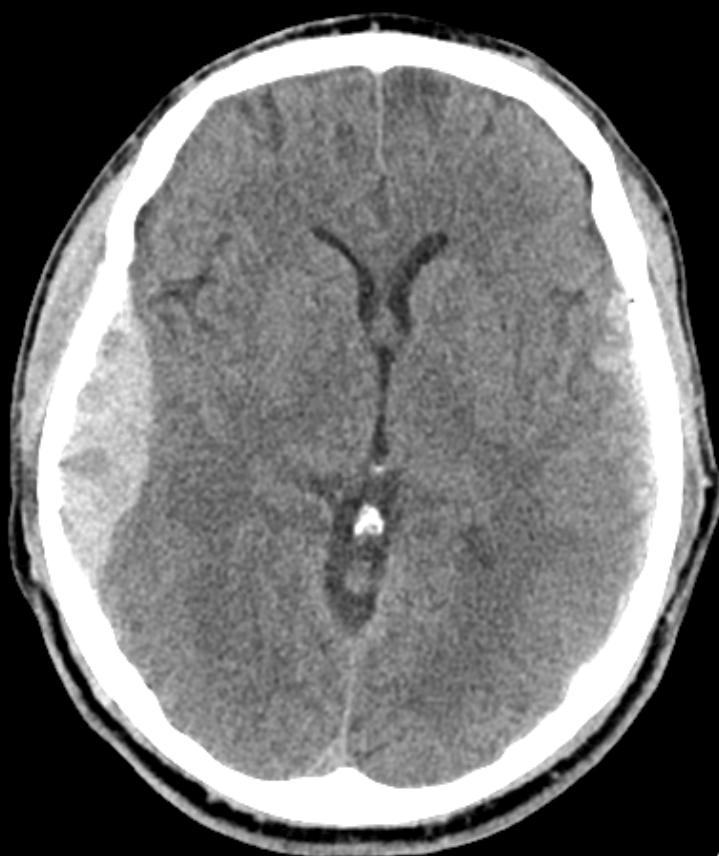

- CCT nativ (Blutung, Ödem, Fraktur, Mittellinienshift)

- Epiduralhämatom: A. meningea media, freies Intervall, CCT: bikonvex → sofortige Trepanation

- Subduralhämatom: Brückenvenen, akut (Stunden) oder chronisch (Wochen), CCT: sichelförmig → Trepanation bei Raumforderung

- ICB: Hypertonie, Antikoagulation, CCT: hyperdens intrazerebral → intensivmedizinisch, Gerinnung korrigieren